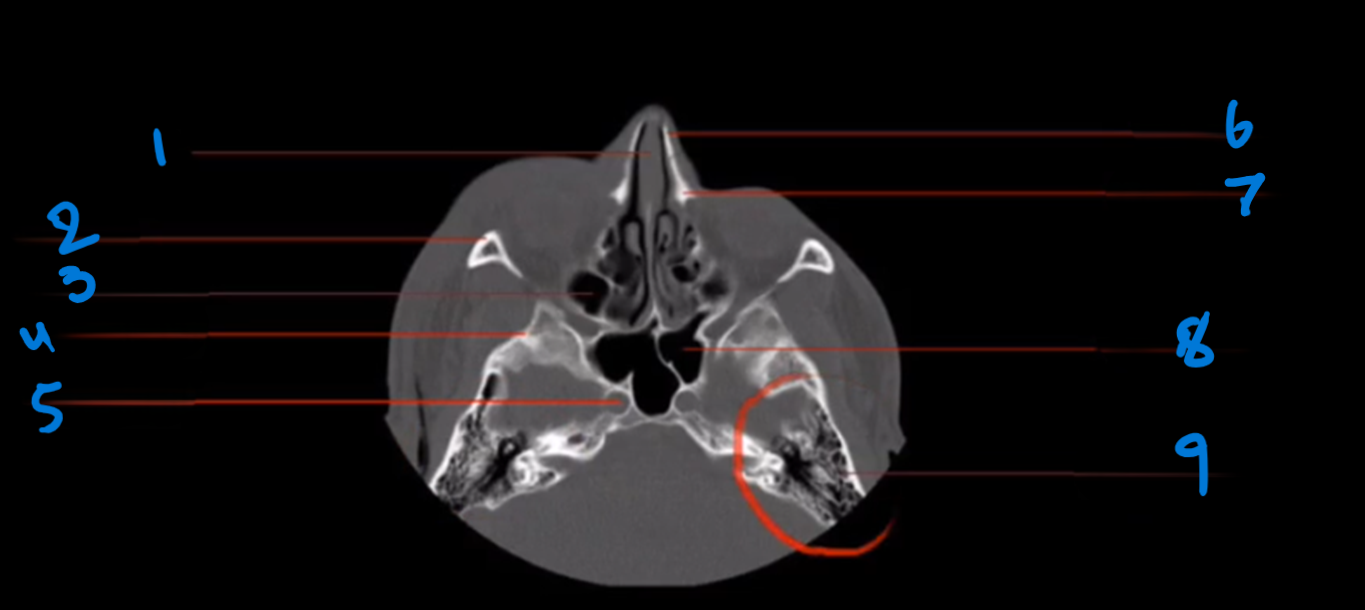

What is the landmark #1 called?

Nasal septum

What is landmark # 2 called?

Zygoma

What is landmark # 3 called?

Maxillary Sinus

WHat is landmark # 4 called?

Sphenoid Bone

What is landmark # 5 called?

Carotid Canal

Nasal bone

What is landmark # 6 called?

Maxillary Bone

WHat is landmark # 7 called?

Sphenoid Sinus

What is landmark # 8 called?

Mastoid air cells, Temporal bone